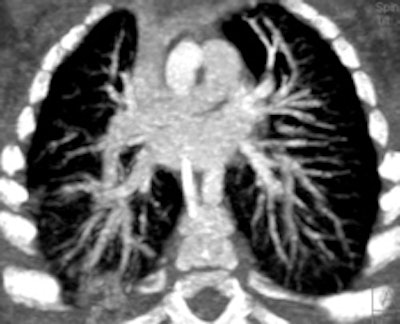

Retrospective ECG-gated study on a 5 year old with severe pulmonary hypertension. The CT images show dilated pulmonary arteries (top left). There is right atrial and ventricular dilatation with hypertrophy and bowing of the interventricular septum into the left ventricle (arrow, top right). There is abnormal arborization and angulation of the peripheral pulmonary arteries (top right, bottom), with multiple peripheral centrilobular nodules with perilesional ground-glass attenuation. Features are in keeping with pulmonary capillary hemangiomatosis.